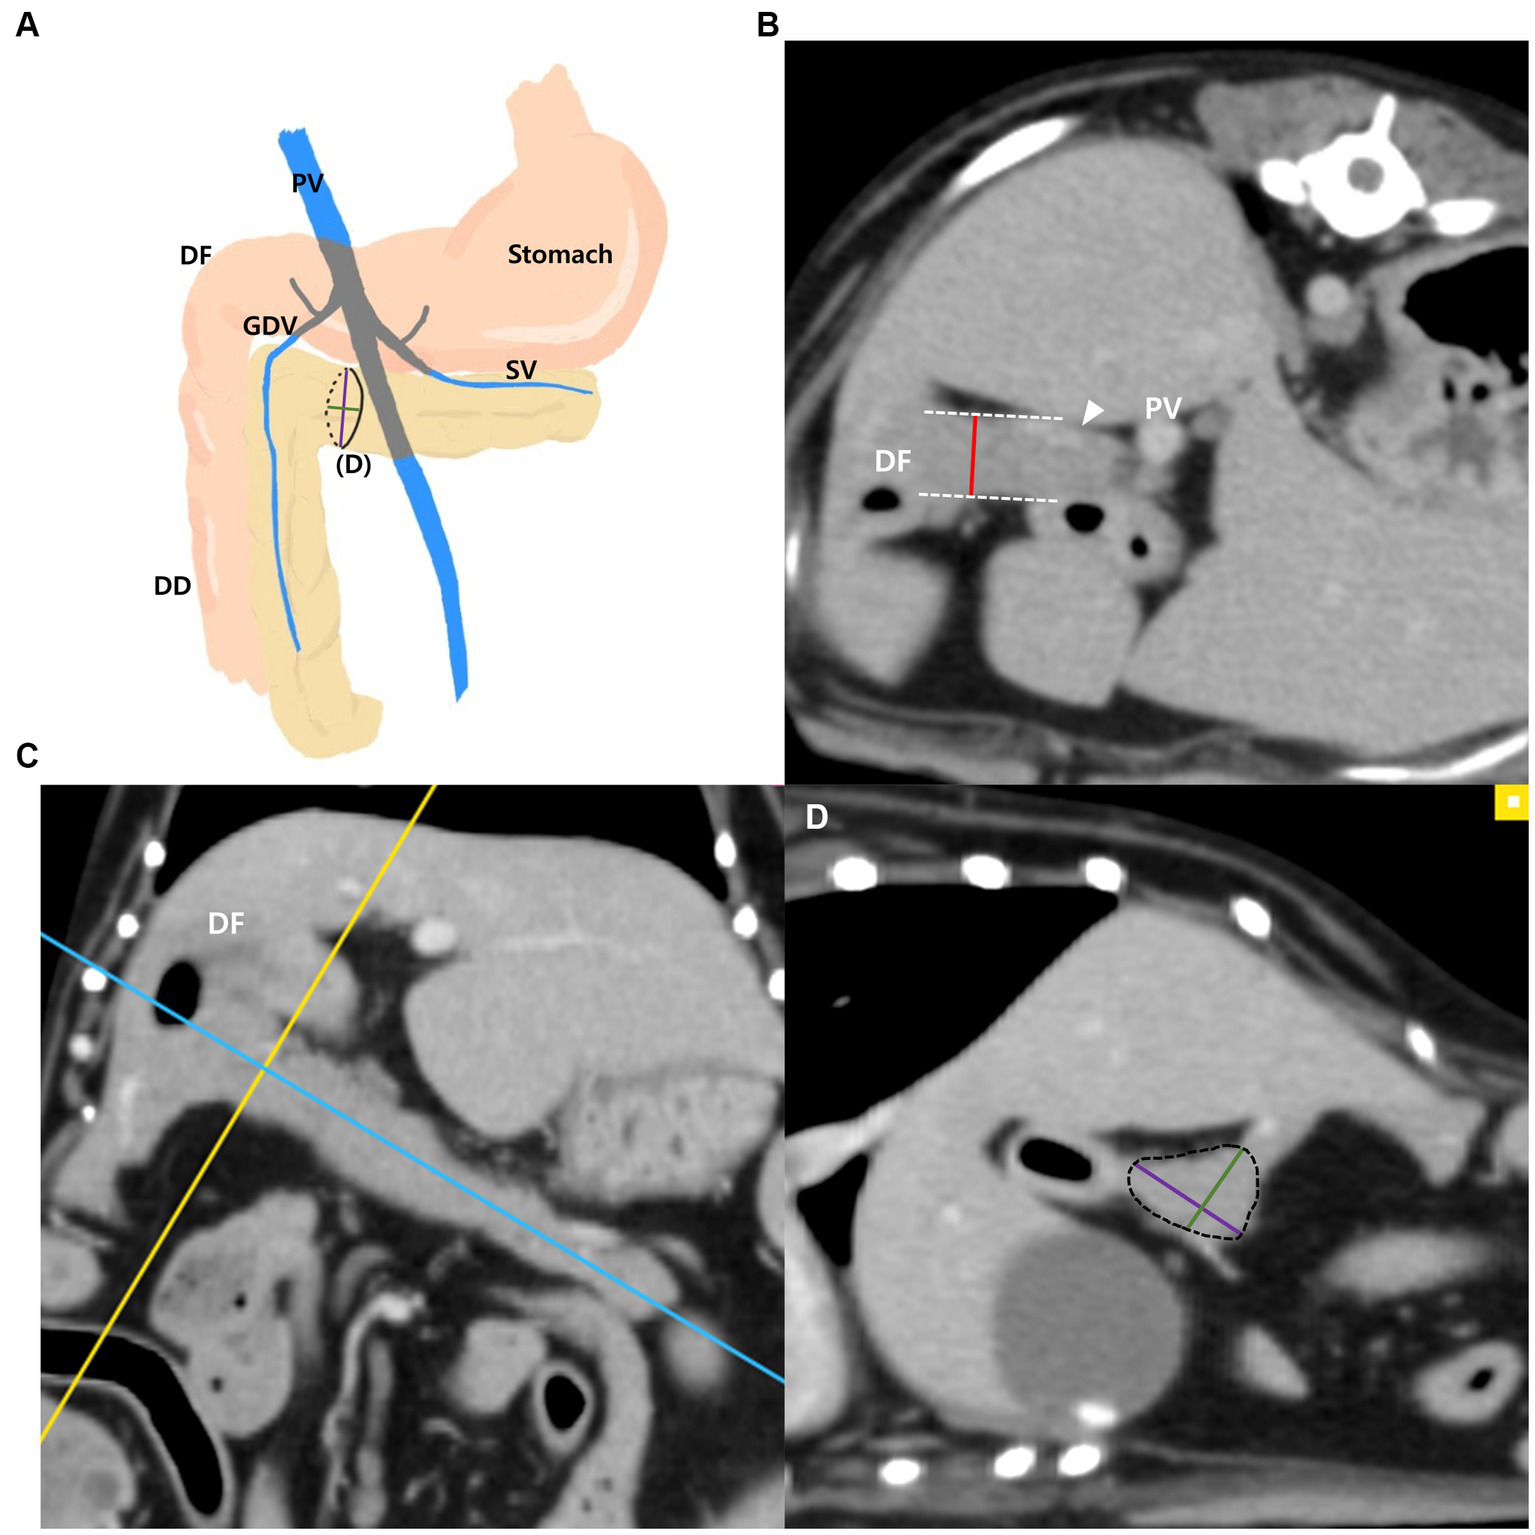

The measurements of the pancreatic body (Figures 1A–D) were taken as follows: the thickness of the pancreatic body was measured at the thickest location in the region adjacent to the duodenal flexure on the transverse plane (Figure 1B). Additionally, in the thickest part, MPR was performed perpendicular to the long axis of the pancreatic body that connecting to the left pancreatic lobe on the dorsal plane (Figure 1C). The long axis of the pancreas was set to be parallel to the midline of the pancreas. In the cross-sectional image (oblique sagittal MPR plane) of the long axis of the pancreatic body, two dimensions perpendicular to each other were measured (Figure 1D). Two dimensions were measured at the longest location and the shorter dimension was called the “short dimension,” and the longer dimension was called the “long dimension” in this study (Figure 1D). The vessels adjacent to or overlapping the pancreas were included in the measurements.

Figure 1

Measurements of the pancreatic body. Schematic illustration of pancreas (A), transverse plane (B), dorsal plane (C) and oblique sagittal MRP plane (D). The thickness of the pancreatic body was measured at the thickest location adjacent to the duodenal flexure (DF) (B). On the dorsal plane (C), long axis (blue line) of pancreas was set to be parallel to the pancreas and through the middle. MPR was performed perpendicular (yellow line) to the long axis (blue line) of the pancreatic body connecting to the left lobe at the thickest part. In the oblique sagittal MPR plane (D), which is cross sectional image at the yellow line, short and long dimensions perpendicular to each other were measured at their longest length (Green, short dimension; Purple, long dimension). PV, portal vein; DF, duodenal flexure; DD, descending duodenum; GDV, gastroduodenal vein (arrowhead); SV, splenic vein.